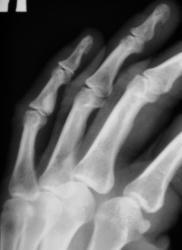

Катенёв Валенти... Дата публикации 19.06.2009, 20:43 Ваше мнение коллеги по поводу локального "уплотнения костной ткани" в средней фаланге 5 пальца левой кисти. Эностоз? Ваше мнение коллеги? Пт, 19/06/2009 - 20:46 #1 Глазков Игорь А... Не на сайте Был на сайте: 11 месяцев 3 недели назад Зарегистрирован: 19.12.2008 - 20:41 Публикации: 1597 что эностоз, но неплохо бы узнать возраст пациента. Прийди к Себе Пт, 19/06/2009 - 20:52 #2 Катенёв Валенти... Не на сайте Был на сайте: 7 лет 3 месяцев назад Зарегистрирован: 22.03.2008 - 22:15 Публикации: 54876 Пациент возраста около 30-ти лет.

Пациент возраста около 30-ти лет.